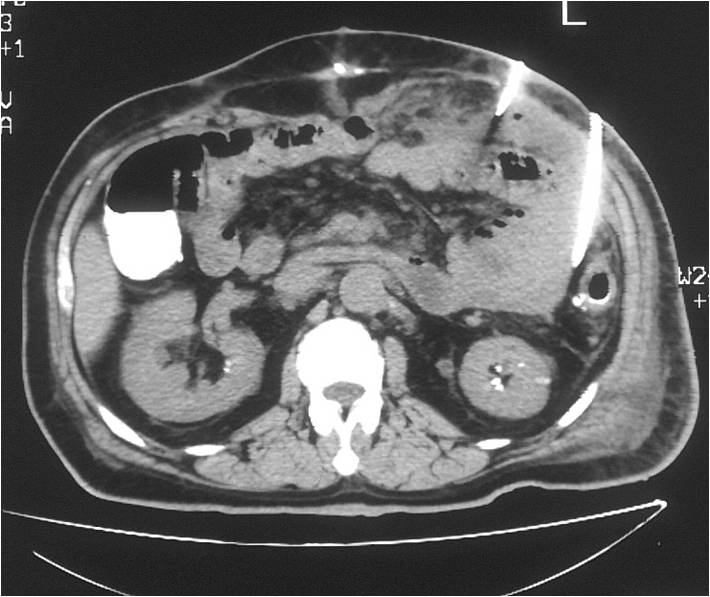

- Large abdominal abscess post- pancreatic surgery

- Successful drainage